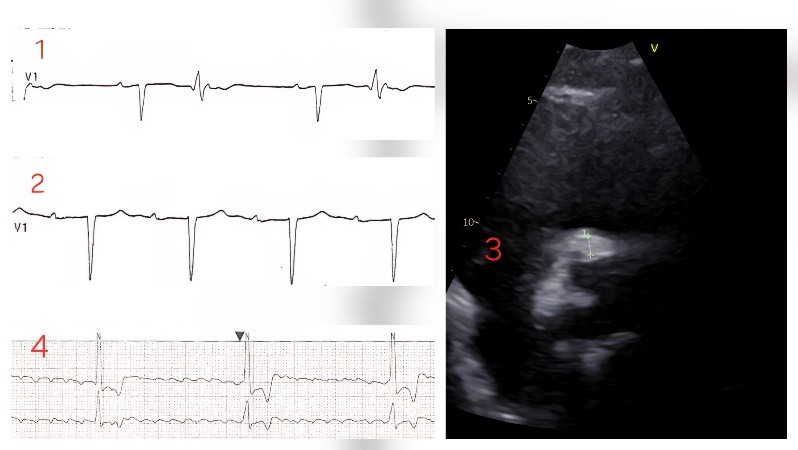

Background: Prosthetic valve endocarditis (PVE) is associated with high morbidity and mortality. Periannular extension with abscess formation is a severe complication that may result in atrioventricular (AV) conduction disturbances due to involvement of the conduction system, often requiring urgent surgical management. Case report: A 75-year-old man, who underwent bicuspid aortic valve replacement with a bioprosthesis in 2014, was admitted with progressive dyspnea, orthopnea, and peripheral edema. ECG showed sinus rhythm with PR 180 ms and ventricular bigeminism (FIG. 1). Transesophageal echocardiography (TEE) revealed thickened bioprosthetic cusps with mild regurgitation. During hospitalization, fever and decompensated heart failure developed, blood cultures grew S. Caprae and a repeat echocardiogram documented severe intraprosthetic regurgitation (PHT 300 ms, abdominal aortic flow reversal). Serial ECGs monitoring showed progressive PR prolongation (360 ms) (FIG. 2) and episodes of 2:1 AV block. Follow-up TEE demonstrated increased thickening and echogenicity of the non-coronary cusp, with perivalvular thickening and a maximum hyper-echogenic area of 8 mm involving the right coronary sinus and the mitro-aortic junction, consistent with endocarditis complicated by annular abscess formation (FIG. 3). During the following days, the patient developed bradyarrhythmic atrial fibrillation with complete AV block (HR 20 bpm) (FIG. 4), requiring temporary pacing. The conduction disorder was considered secondary to annular abscess extension. Given the rapid clinical deterioration, after having discussed the case in Heart Team, a urgent redo aortic valve replacement with annular debridement was performed. Postoperatively, sinus rhythm was restored with residual first-degree AV block without episodes of advanced conduction abnormalities. Conclusion: This case report illustrates the possible rapid progression of a prosthetic valve endocarditis complicated by annular abscess and advanced conduction disturbances. This emphasizes the need for prompt diagnosis, Heart Team evaluation, and early surgical intervention.